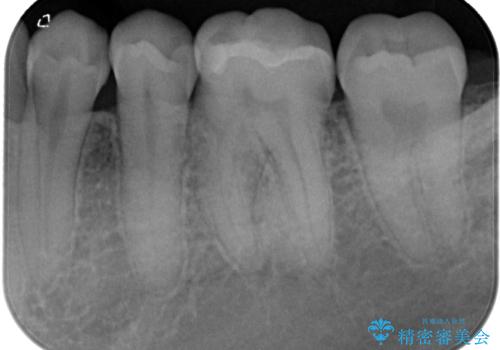

- 数年前他院にて治療した銀歯をやり替え希望の患者様です。

拡大鏡下で、銀歯、むし歯の除去を行い、セラミックインレーに適した形に整えました。